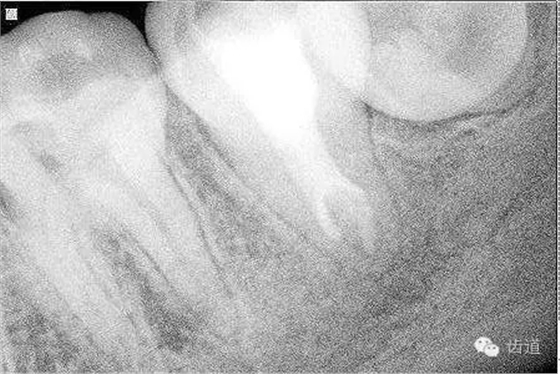

2. 術(shù)前X片

可見37根管影像清晰,根中上三分之二粗大,根尖三分一分為近遠(yuǎn)中兩根管,形態(tài)均呈弧形,根尖周膜連續(xù)性中斷,根尖周透射影明顯